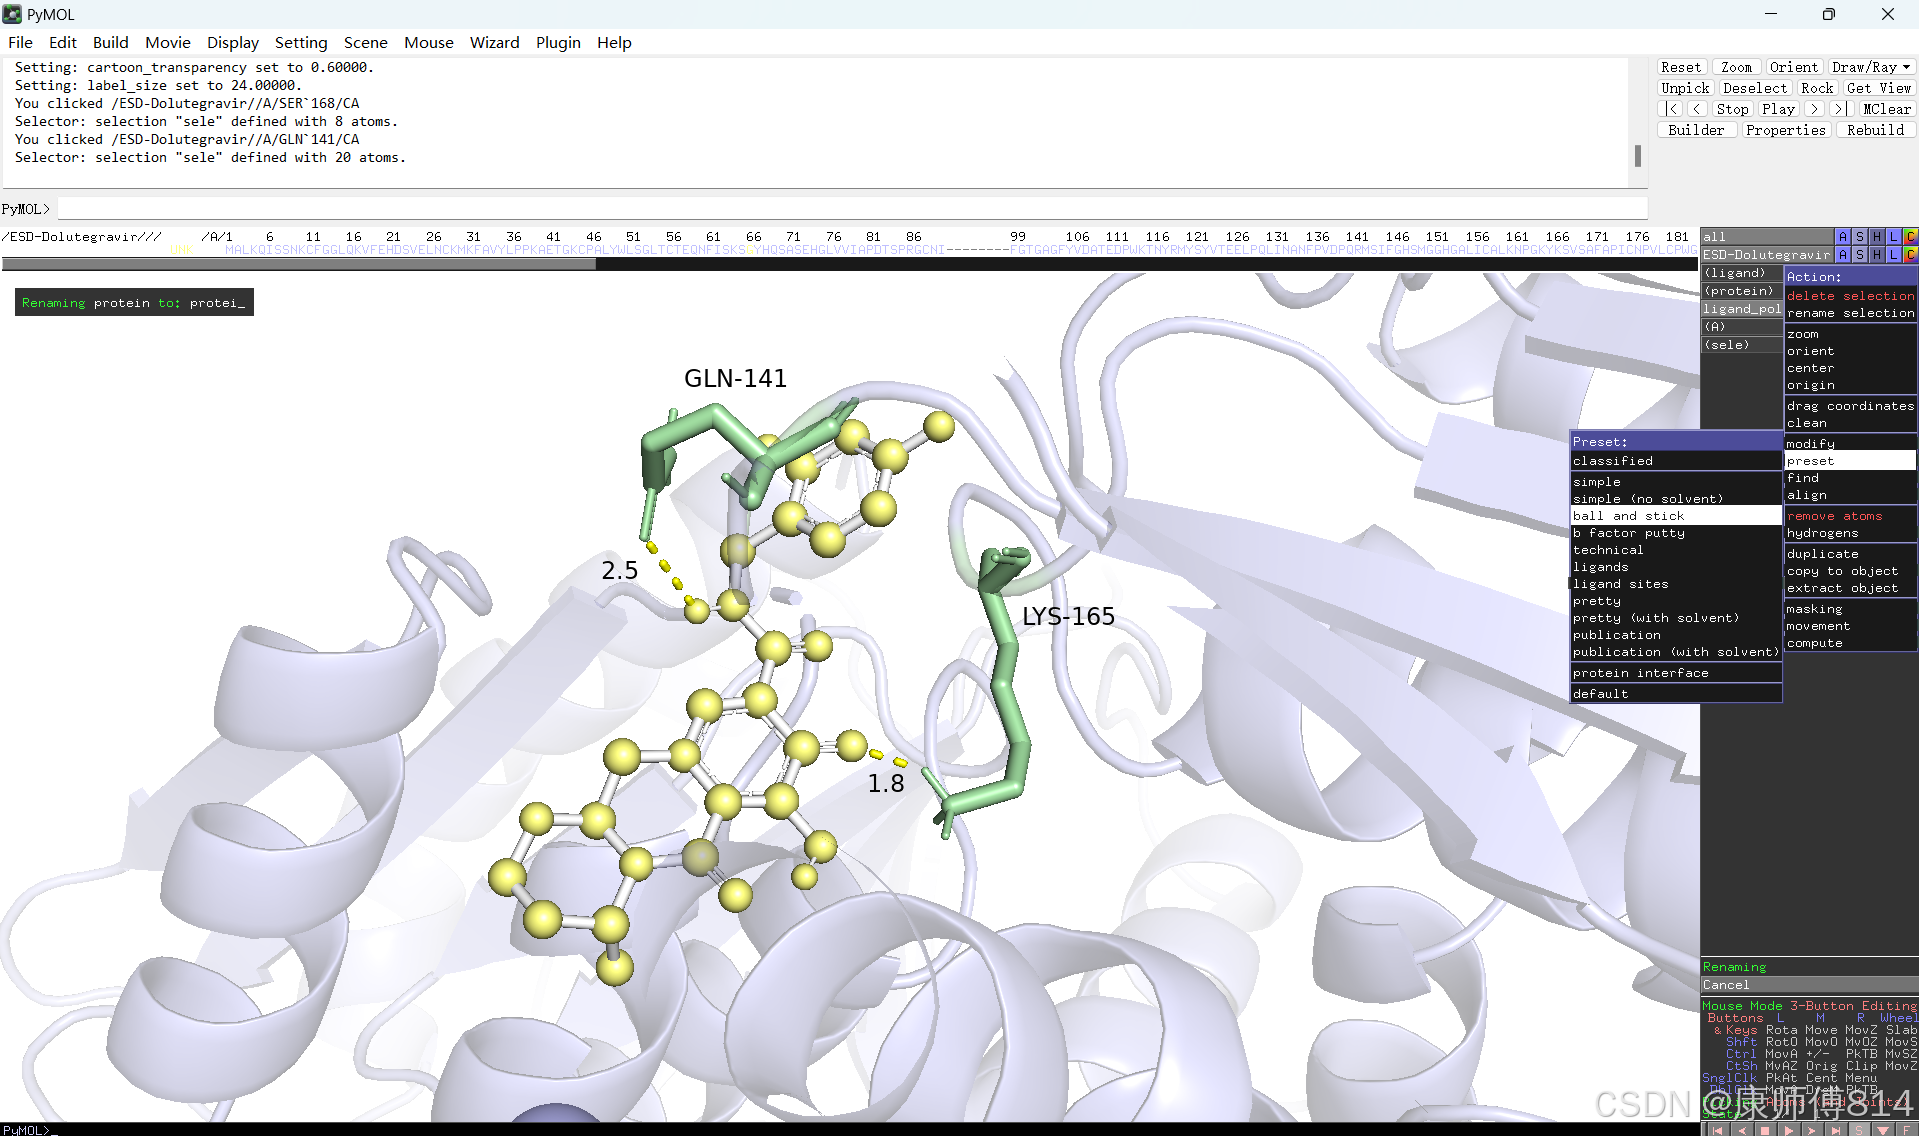

#选中蛋白,点击show-sticks显示氨基酸棍状结构,右下角Selecting修改为Residues模式,选中与小分子连接的氨基酸残基,命名为A,并更改颜色

#点击蛋白,点击H-sicks隐藏蛋白棍状结构,然后显示小分子结合位点氨基酸残基棍状结构

#此时展示分子对接的基本要素已经形成,后续可根据需要修改背景颜色、显示氨基酸残基名字以及氢键键能等等,这里不再赘述

结果演示